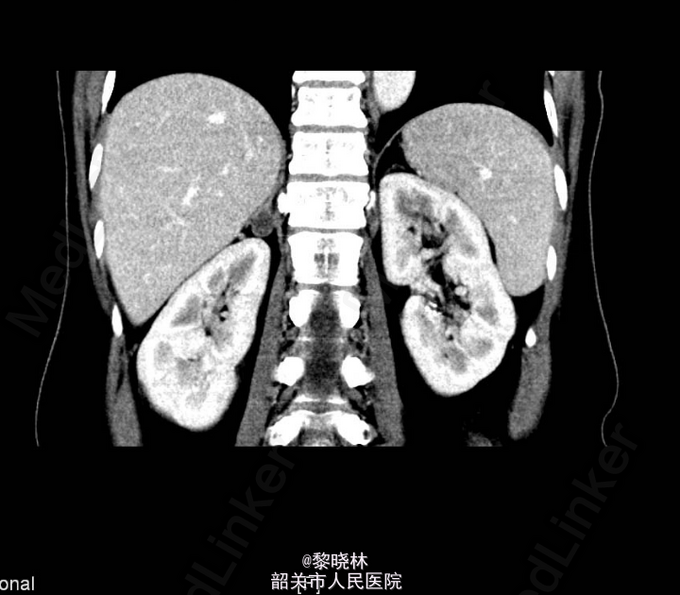

入院查体:BP182/111mmHg,余无特殊。辅助检查门诊CT示双肾+肾上腺螺旋CT平扫+增强扫描(中腹)检查所见:1、右肾上腺结节,考虑腺瘤;左肾上腺增生。2、左肾下盏结石。3、小副脾。

诊断:高血压查因:肾上腺瘤? 入院后查尿蛋白定量/尿肌酐比值 尿总蛋白0.030g/L,尿肌酐4019.000umol/L。高血压三项 醛固酮547.930pg/ml,肾素浓度23.520pg/ml,血管紧张素II137.070pg/ml。 血清钾、钠、氯测定 钾2.930mmol/L。血常规、尿常规、大便常规、生化、甲功、肿瘤标志物、胸片、心电图均未见明显异常。排除手术禁忌症后,于2015-03-16行右侧后腹腔镜下肾上腺肿物切除术,术后病理提示“右侧肾上腺皮质腺瘤”。